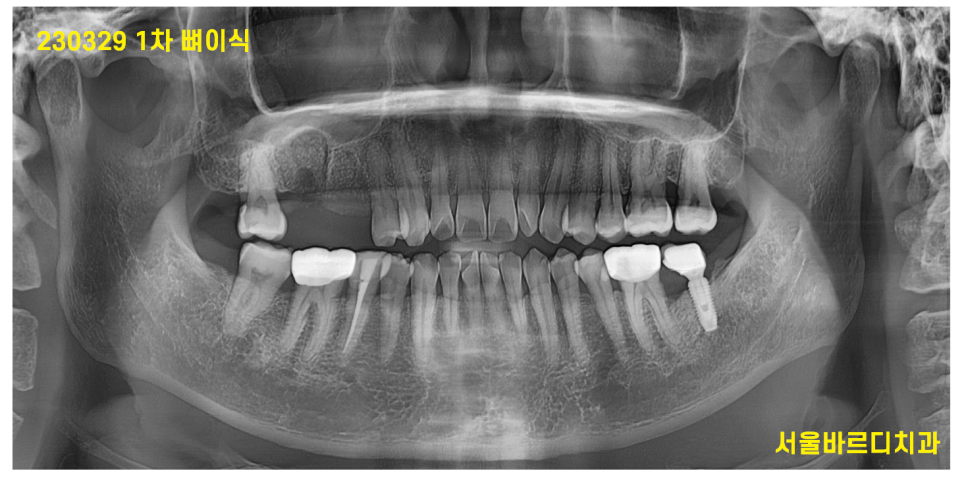

230329

우선 이를 뽑고 염증 덩어리들을 제거

깨끗해진 환경에 뼈 이식을 진행하였습니다.

이때만 해도 이 뺀 곳에 뼈가 녹은 흔적들이 그대로 보이네요~~